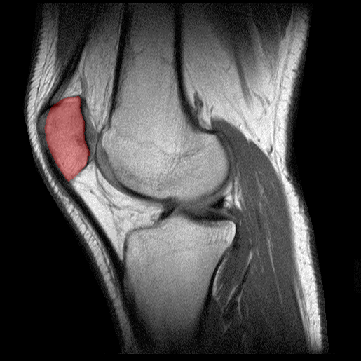

ROTULA

La rótula

es un hueso plano y redondeado que se encuentra incluído en el

tendón terminal del músculo cuadriceps femoral y está

situado por delante de la extremidad inferior del fémur